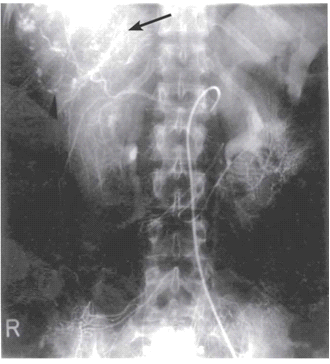

באנגיוגרפיה ניתן לראות גוש וסקולרי ביותר (תצלום 18.10).